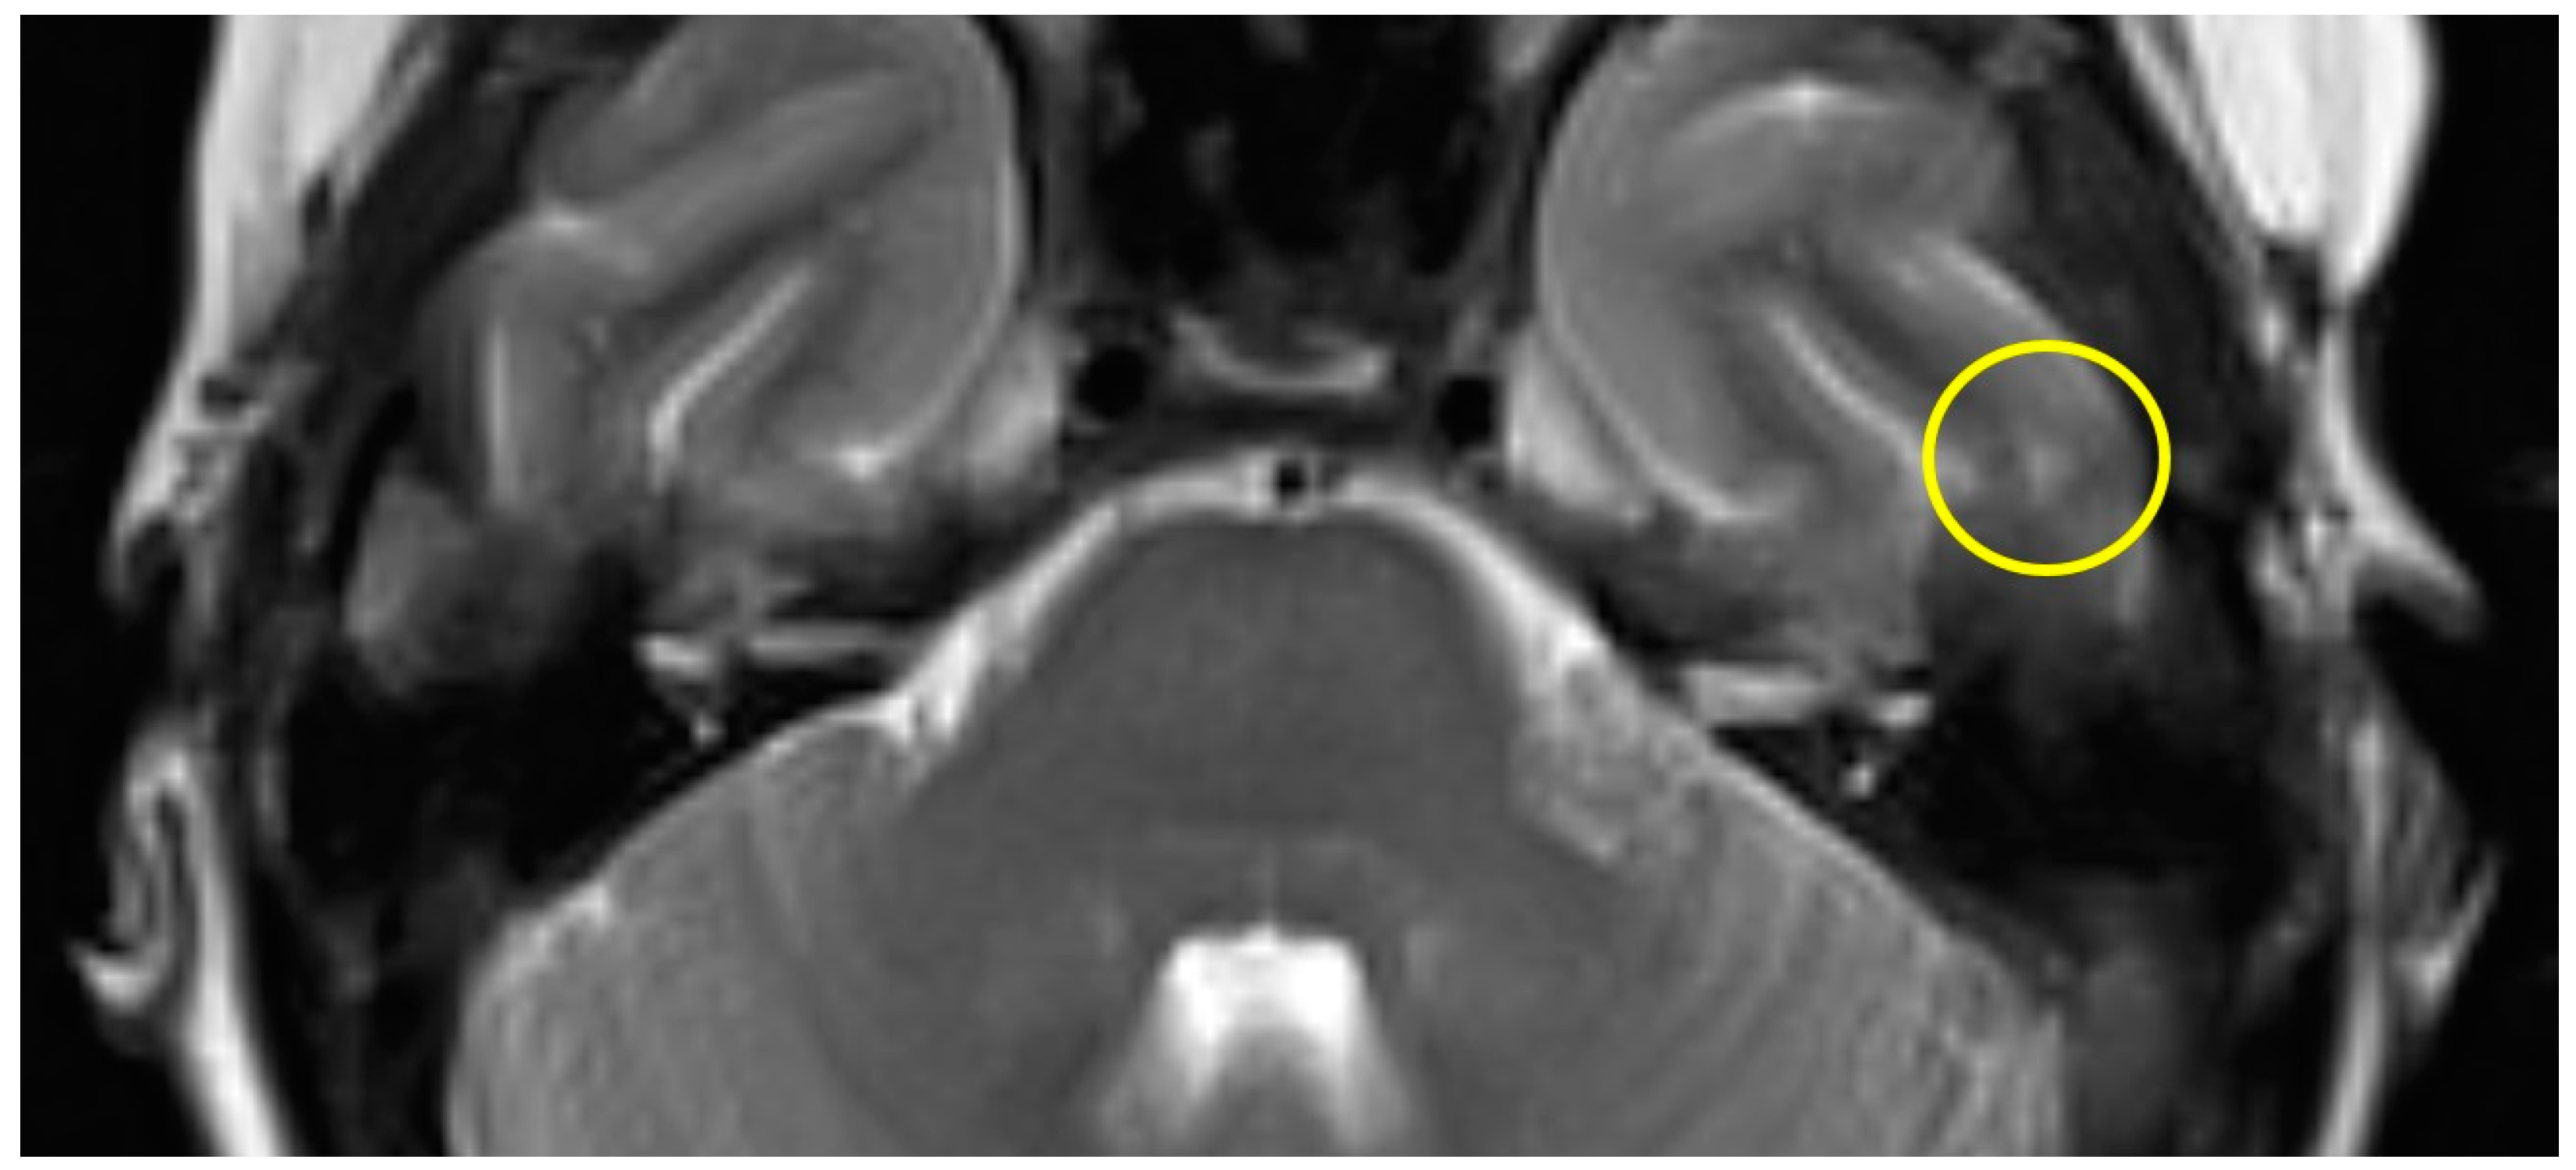

The first postoperative MR imaging of patient #3 was made 11 months after surgery and showed a very discrete focal hyperintensity on axial T2w imaging in the left temporal lobe (Figure 3). In patient #4 (Figure 4), a slight rim of gliosis was detectable on the left side in the follow-up imaging 12 months postoperatively, which can be seen in coronal T2w FLAIR (Fluid-Attenuated Inversion Recovery) imaging.

Figure 3.

Axial T2w MR imaging of patient #3 (yellow circle = gliosis). Supplementary MR imaging can be downloaded.